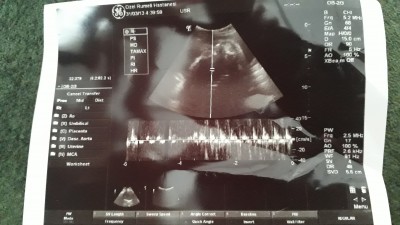

Kizlar bugun doktor muayenem vardi 28+3 gunluk hamileyim doktor 1440 gr kilosunu dedi boyunu soylemedi boyu nerde yaziyor acaba hamilelik boyunca su ana kadar 3 kilo almisim istahsizlik ve kalca agrilarim var magnezyum verdi insallah duzelirim

Resim net değil ki okunmuyor

Tekrar yukledim ama simdi gorukuyormu

Resim çok silik yakınlaşınca

FL yazan bi yer olmasi lazim ordaki degeri 7 ile carpimi bebegin boyunu veriyor

Ben bulamadim fl yi tekrar yukledim bakarmisiniz

Bunda fl ölçüsü yok sadece bu mu var elinizde

Evet malesef agrilarim var diye doktorumun dedigini tam anlayamadim bebek iyi kilosu iyi dedigi kaldi aklimda

Canim öyle dediyse kafama takma sıkınti olsa söylerdi doktorun merak etme tabi insan merak ediyor ama kilosu az olsaydi doktorun uyarirdi seni ve mutlaka kalirdi aklinda merak etme